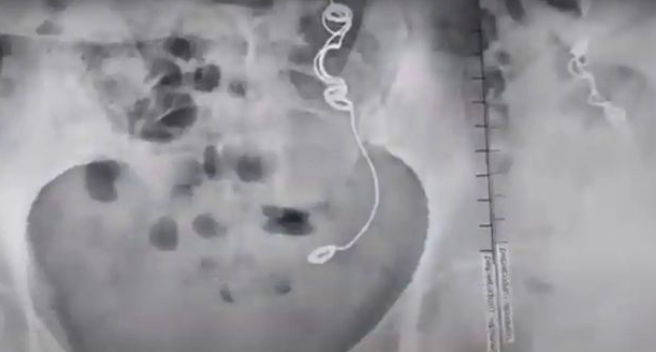

艾德琳達崩潰表示:「我跟醫生都不敢相信眼前所見!」讓人傻眼的是,她去找當初幫她結紮的醫生,對方斬釘截鐵否認失誤,強調自己絕對不可能出現這樣的醫療疏失,還暗指是她自己將針線吞下肚。

面對這情況,專家憂心表示,異物長年留在體內是非常危險的事,嚴重的話還會導致癌症發生,艾德琳達只能等待醫生評估,確定她是否可以動手術將異物取出,然而發生這樣的事,白白受苦10年,真的希望最後的結果是好的啊!